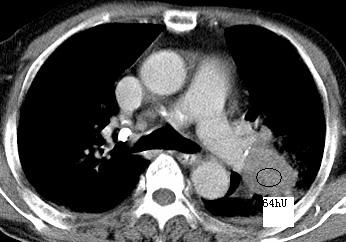

以下是引用xianxianzhongyi在2008-4-20 14:44:00的发言:[br]本人愚见:次病例短短两月的时间,呈现如此大面积实变,病变增长过于迅速,此其一。其二,病变在动脉早期既有明显强化。其三,左上叶后段及下叶背段多叶受累。其四,肺门及纵隔内未见明显肿大的淋巴结。估计层面较厚段支气管显示不清。 诊断:炎性实变可能性大。

以下是引用光影相伴在2008-4-20 14:39:00的发言:[br]支持:1)左侧中央型肺癌伴左肺上叶阻塞性肺炎。、[br] 2)双侧少量胸腔积液。